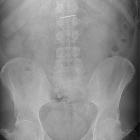

Zahnarztbohrer verschluckt

Two plain radiographs are recommended to accurately demonstrate the size, shape, and location of the rectal foreign body. This should be performed before a digital examination to prevent staff-related injuries from sharper foreign bodies.

The investigation of foreign bodies relies heavily on radiology and every foreign body will have an optimal modality for investigation . Metal, glass, and stone can be visualized very well using conventional plain film radiography, whereas more organic structures, such as wood, may require further imaging such as ultrasonography.

Plain radiographs

The radiological appearance in plain radiography of foreign bodies is dependent on three factors: the x-ray attenuation of the foreign body, the surrounding structures and any overlying structures that may veil the object.